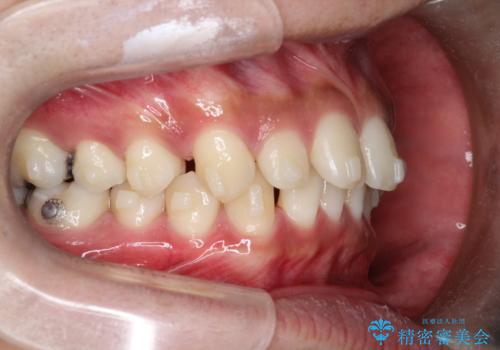

【インビザライン】空隙歯列の矯正

- 前歯の隙間を主訴に来院されました。

なるべく目立たない治療を希望されましたので、インビザラインにて治療を行なっております。

単純に前歯の隙間の閉鎖をしてしまうと、前歯に早期接触が生まれ、臼歯が噛まなくなってしまいます。適切な治療計画を立てることで、噛み合わせも良好な結果を得ることができました。